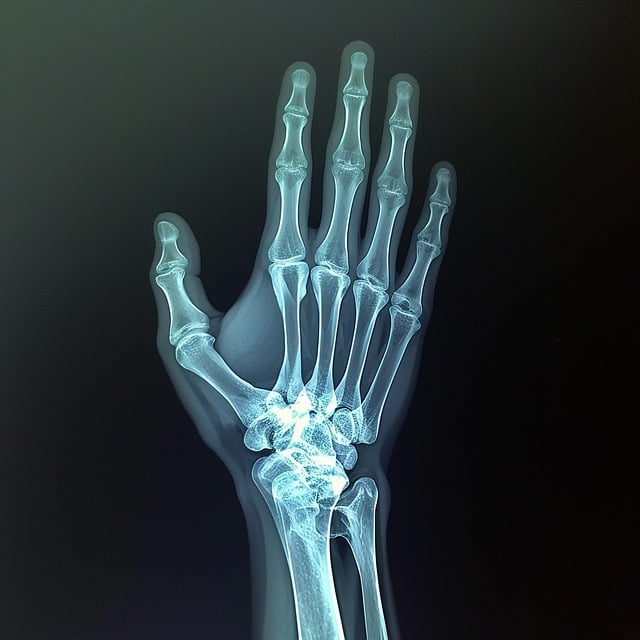

필자가 손 검사를 했을 때 가장 먼저 촬영한 방법입니다. PA Projection을 촬영하는 이유는 손허리뼈, 손가락뼈, 손목뼈 등 손의 모든 관절을 관찰하기 위해서이며, 이때 자뼈, 노뼈, 엄지의 사선 방향 촬영상을 볼 수 있습니다.

환자를 촬영대 끝에 앉도록 하여 팔을 직각에 가깝게 굽히게 하고 손과 아래팔을 편안한 자세로 촬영대 위에 놓고 손바닥이 아래로 향하게 해서 손바닥이 상 수용체 면에 밀착되도록 합니다. 이때 상 수용체의 반쪽에 손의 중앙과 손목을 둡니다. 상 수용체는 X선을 조사했을 때 촬영된 사진의 장축에 손과 아래팔의 장축이 일치되도록 하고 손가락들은 약간 펼쳐지도록 합니다. 중심 X선은 셋째 손허리손가락관절에 수직이 되게 조사합니다. X선관 초점과 영상 면 사이 거리는 100cm로 합니다. 만약 양손이나 손목을 촬영할 경우 각 위치에 따라 정확한 중심 X선의 위치를 조절하여 촬영합니다.

상 수용체의 장축에 손과 손목의 장축이 일치하도록 촬영되어야 하며 손이 회전되지 않아야 하고 손허리뼈와 손가락뼈와 연부 조직이 대칭으로 나타나야 합니다. 이때 첫째 손허리뼈, 엄지의 손가락뼈는 회전하므로 제외합니다.

연부 조직이 겹치지 않도록 손가락은 펼쳐져 있어야 합니다. 손이 펴진 상태에서 손허리손가락관절과 손가락뼈사이관절 사이가 분리되어 촬영되어야 합니다.

손과 손목, 아래팔 끝이 조절된 조사 범위 안에 모두 포함되어 나타나야 합니다.

조사 범위의 중앙에 셋째 손허리손가락관절이 나타나야 합니다.

움직임이 없는 상태에서 가장 적당한 노출로 연부 조직이 선명하고 깨끗하게 나타나며 미세구조의 음영이 나타나야 합니다.